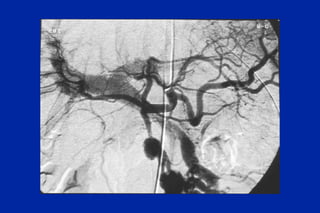

Este documento resume los principales tipos y técnicas de angiografía. Describe brevemente la angiografía, arteriografía, flebografía y linfografía, así como las técnicas de contraste y materiales utilizados. También explica los principales accesos vasculares, la técnica de Seldinger, la angiografía por sustracción digital y algunas técnicas endovasculares comunes.